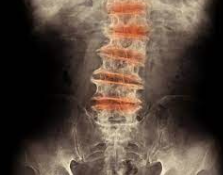

この際、骨折、脱臼のないことをX線撮影によりたしかめる必要があります。